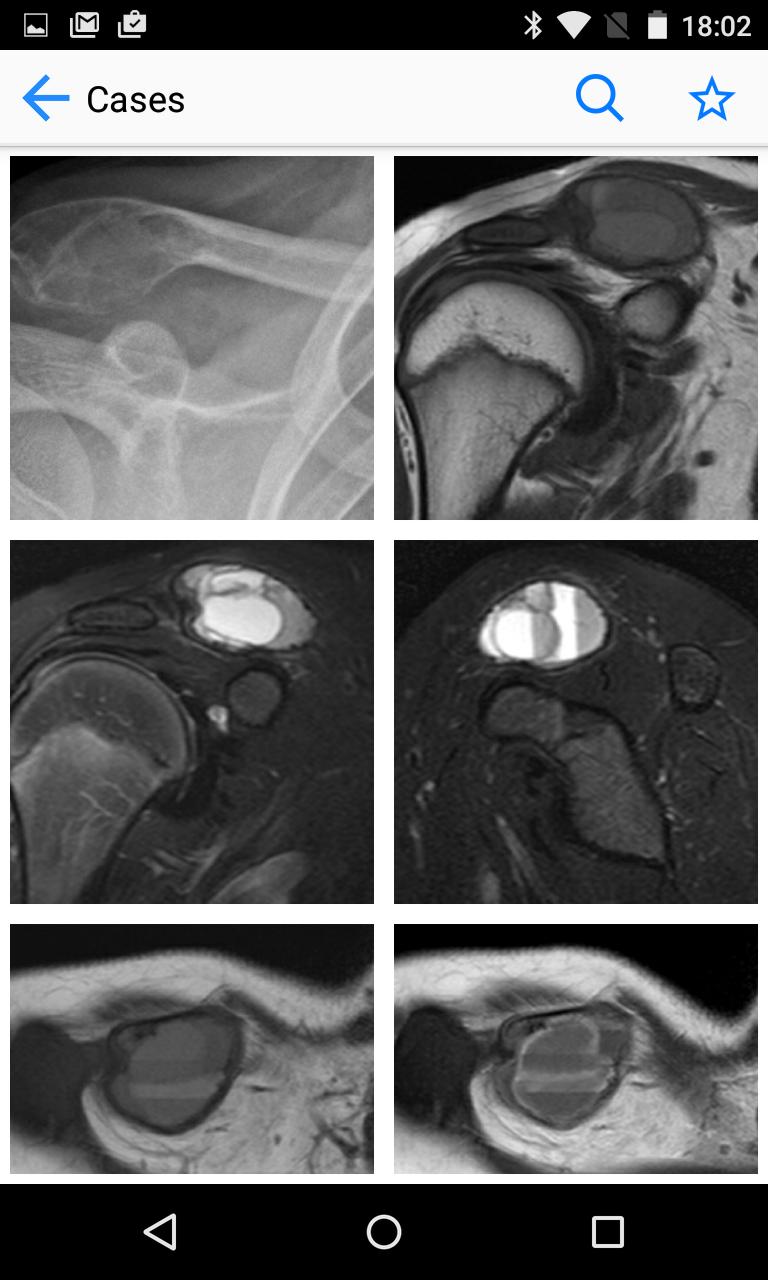

BoSTT bringt dem Benutzer eine echte Erfahrung mit häufigen und seltenen, typischen und ungewöhnlicheren Fällen von Knochen- und Weichgewebe -Tumoren. Jeder Fall hat eine klinische Anamnese, hochauflösende Radiologie- und Pathologie -Bilder, Diagnose, Behandlungs- und Lernpunkte.